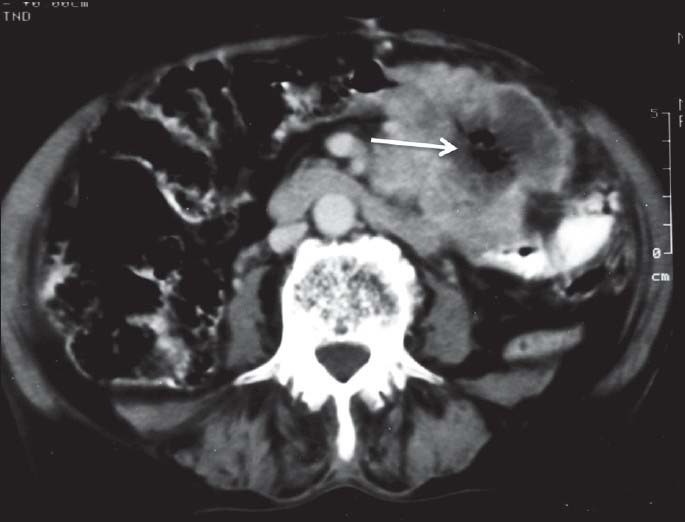

| Figure 2:Ileal gastrointestinal stromal tumor in a 45-year-old male — axial contrast-enhanced computed tomography image showing heterogeneously enhancing exophytic mass lesion (black arrowhead) arising from ileal loop causing mild aneurysmal dilatation (white arrowhead)

| Figure 2:Ileal gastrointestinal stromal tumor in a 45-year-old male — axial contrast-enhanced computed tomography image showing heterogeneously enhancing exophytic mass lesion (black arrowhead) arising from ileal loop causing mild aneurysmal dilatation (white arrowhead)

Gastrointestinal stromal tumors most affects people of age group 40-70 years old. Male to female incidence is now considered to be equal. Statistically, between 5000 and 10,000 people develop this tumor worldwide with nearly 1000-2000 new cases/year in the United States. GISTs accounts for 1-3% of all gastrointestinal tumors. GISTs can involve the gastrointestinal tract anywhere from esophagus to anus — stomach (37-70%), small bowel (20-33%), duodenum (9%), anorectum (5-7%), colon (4%) and esophagus (<2 href="https://www.ncbi.nlm.nih.gov/pmc/articles/PMC4152631/figure/F1/" target="figure" class="fig-table-link figpopup" rid-figpopup="F1" rid-ob="ob-F1" co-legend-rid="lgnd_F1" xss=removed>[Figures11--55].[1] Other atypical locations are omentum, mesentery and retroperitoneum [Figures [Figures66--88].[2] The histologic classification is based on the predominant cell type — spindle cell, epithelioid cell or mixed cell type. The spindle cell type accounts for about 75% of GISTs and is also the most common type of GIST at other sites.

On imaging, GISTs may be submucosal, intramural or subserosal. Findings on barium studies are often subtle than seen on computed tomography (CT) as majority of them are exophytic in nature. On CT, small GISTs are usually well-defined, solid mass showing homogenous enhancement [Figure 9]. Calcifications may occasionally be present. Large tumors show areas of hemorrhage, cystic/necrotic areas and heterogeneous enhancement. Neovascularity may be seen within the tumor after contrast administration [Figure 10]. Thrombosis of mesenteric vessels is uncommon. Rarely, these tumors may be entirely cystic [Figure 11]. Cavitory nature with air and contrast within the mass is suggestive of mucosal ulceration with fistulous communication of necrotic cavity with the bowel lumen [Figure 12].[3,4] Collection of air in the nondependent aspect of larger cavitating tumors with necrosis is known as the “Toricelli-Bernouilli” crescentic necrosis sign [Figure 13].[5] Uncommon features with GIST are presence of ascites, lymphadenopathy, intestinal obstruction and metastases in lungs [Figure 14]. Crucial role lies in differentiation of benign versus malignant GISTs. Features associated with poor prognosis include distal location, size and high mitotic activity with the exception of esophageal GISTs.[6] Benign lesions are usually <2>5 cm.[7] Smaller tumors should be classified as at lower risk for malignancy rather than as benign. Tumor necrosis, cystic change, nuclear atypia, tumor vascularity, and degree of staining for CD117 are unreliable predictors of malignancy.[8] Metastases are most common in the liver, mesentery, and peritoneum [Figure 15].[9,10] Calcification is usually seen in metastases after specific chemotherapy.